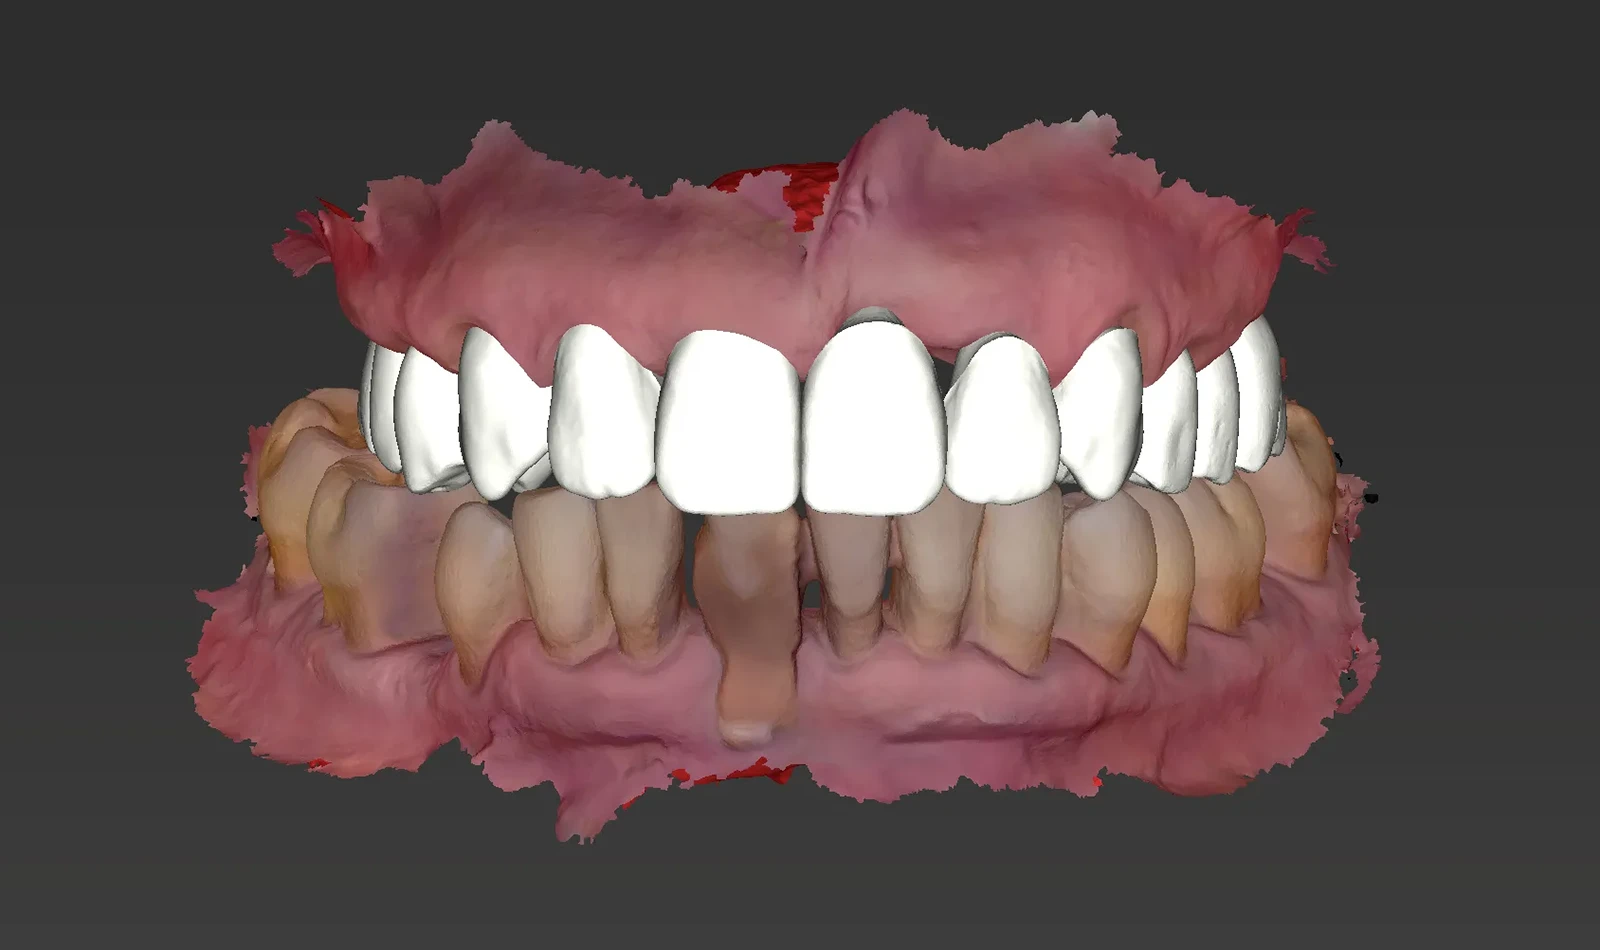

De 61 años nos visita con dientes dañados por caries y una prótesis antigua que ya no podía utilizar. Gracias a la planificación digital y la cirugía guiada, realizamos las extracciones y colocamos implantes con una prótesis fija el mismo día. Recuperó su sonrisa y la confianza de inmediato.